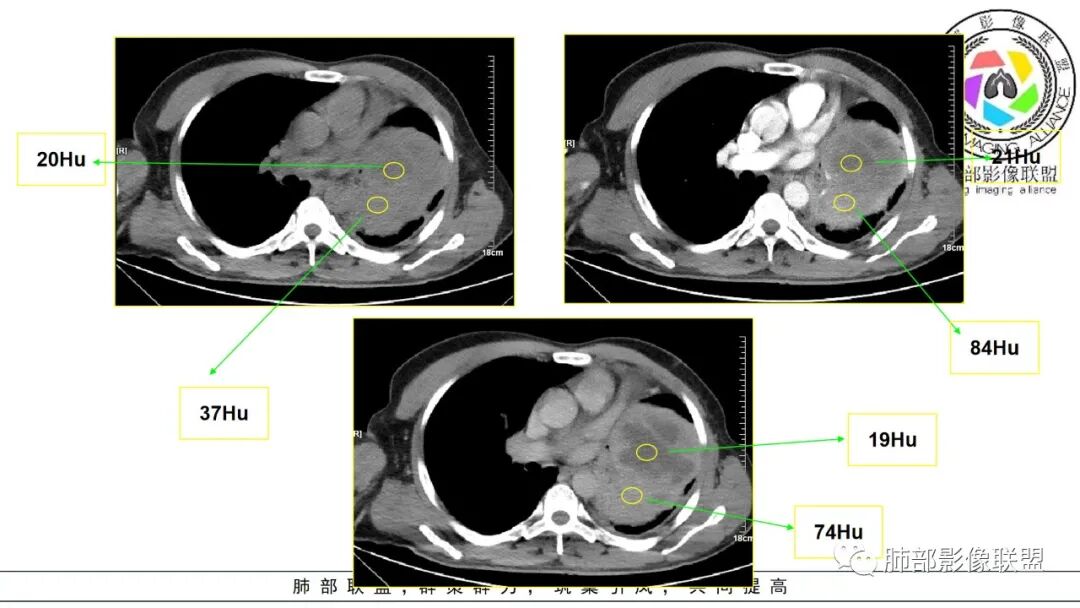

好发于肺胸壁交界区或纵隔交界区,病灶部位对病灶性质判断有较大价值。多单发,有包膜,边界清。

密度:与肿瘤细胞疏松或密集、胶原纤维含量、出血、坏死、囊变及黏液变性等有关。镜下由梭形细胞组成、细胞间由胶原纤维沉积,CT平扫肿瘤实性部分为等、稍低密度,胶原纤维易发生黏液变性或囊变,导致密度不均匀,较少出现钙化。一般肿瘤小,密度多均匀,肿瘤大,多发生坏死、囊变,密度多不均匀。

强化方式:多均匀或不均匀明显强化,增强肿瘤内可见迂曲血管影(蛇纹血管等),肿瘤较大可见“地图样”强化。

3.病灶密度不均,轻度强化,坏死或液化范围甚大,边界可分辨,部分“壁”可见钙化。